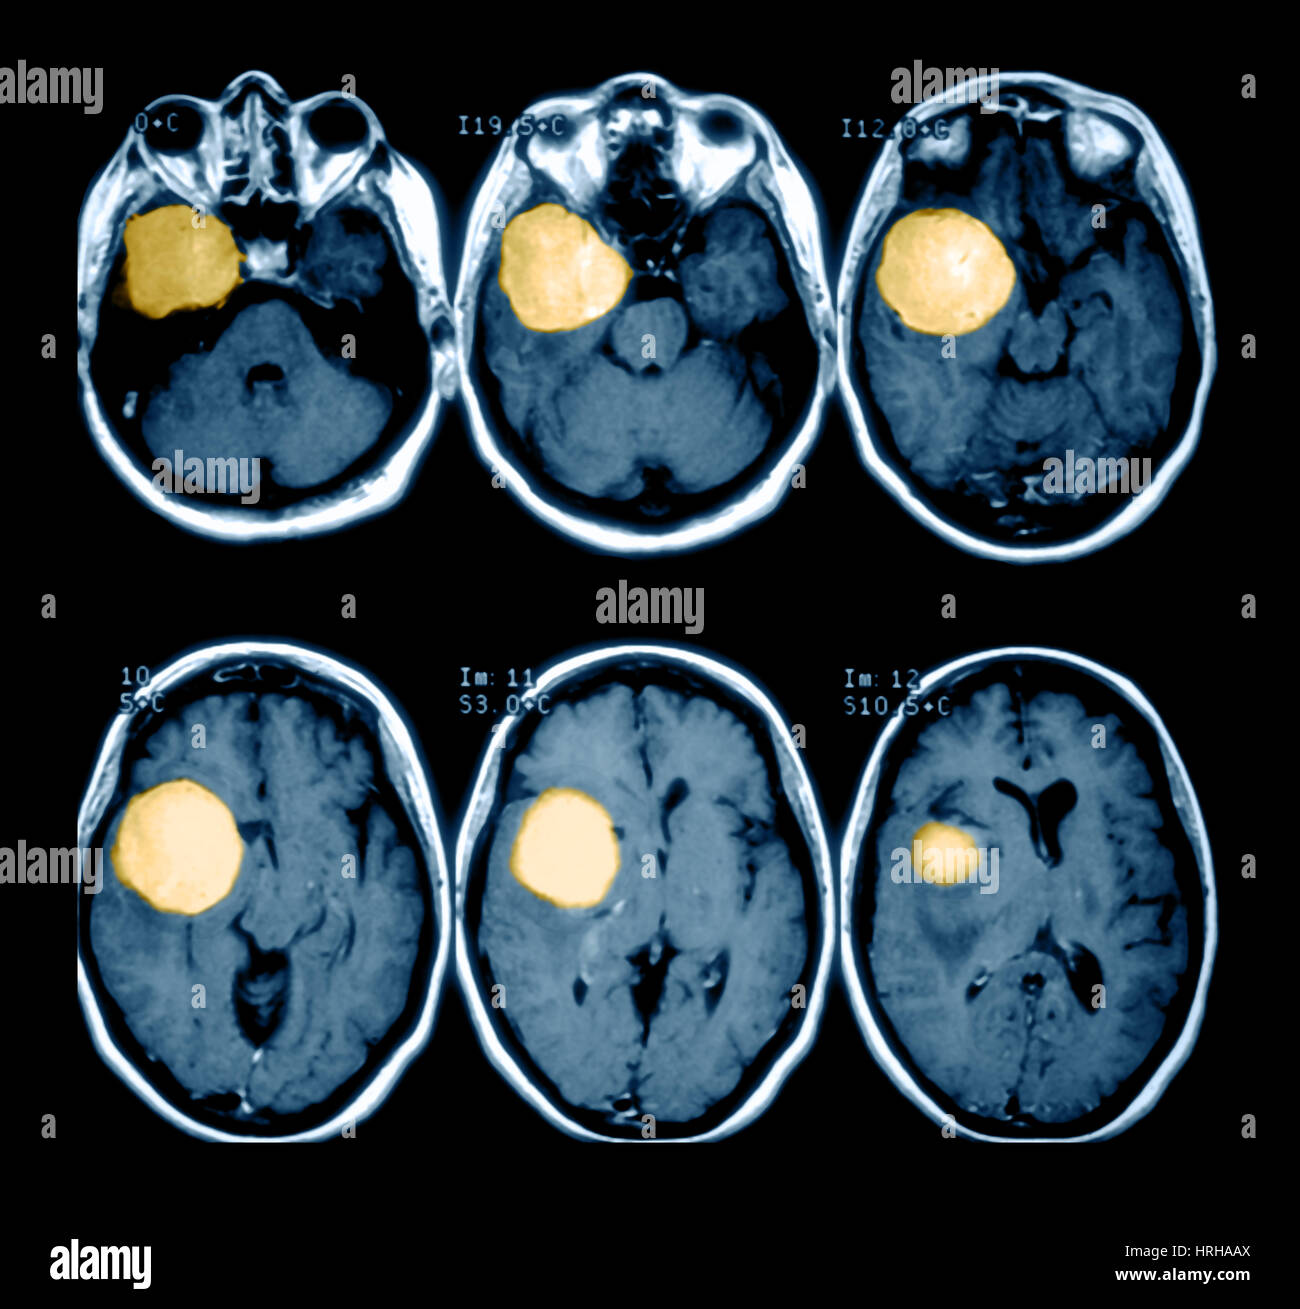

Les symptômes des cancers du cerveau dépendent de la localisation exacte de la tumeur j'ai en 1997 été opéré d'une tumeur de 45mm au cerveau, on l'appelle macroadenome hypophisaire expansif a prolactine, on me l'a irradié et ce n'est selon mon specialiste que ne peut plus voir, pas guérri. D'autres affections médicales peuvent causer les mêmes symptômes que la tumeur au cerveau ou à la moelle épinière.

Tumeur au cerveau Photo Stock Alamy. j'ai en 1997 été opéré d'une tumeur de 45mm au cerveau, on l'appelle macroadenome hypophisaire expansif a prolactine, on me l'a irradié et ce n'est selon mon specialiste que ne peut plus voir, pas guérri. Medisite vous explique comment les identifier avec l'expertise du Dr Julien Geffrelot,.